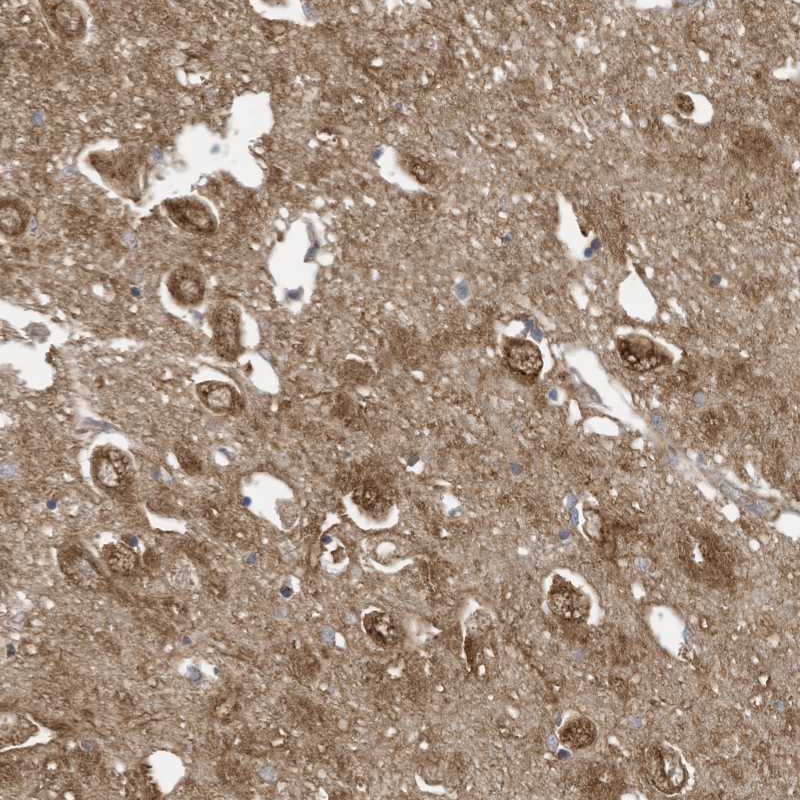

Immunohistochemical staining of human hippocampus shows strong cytoplasmic positivity in neuronal cells.